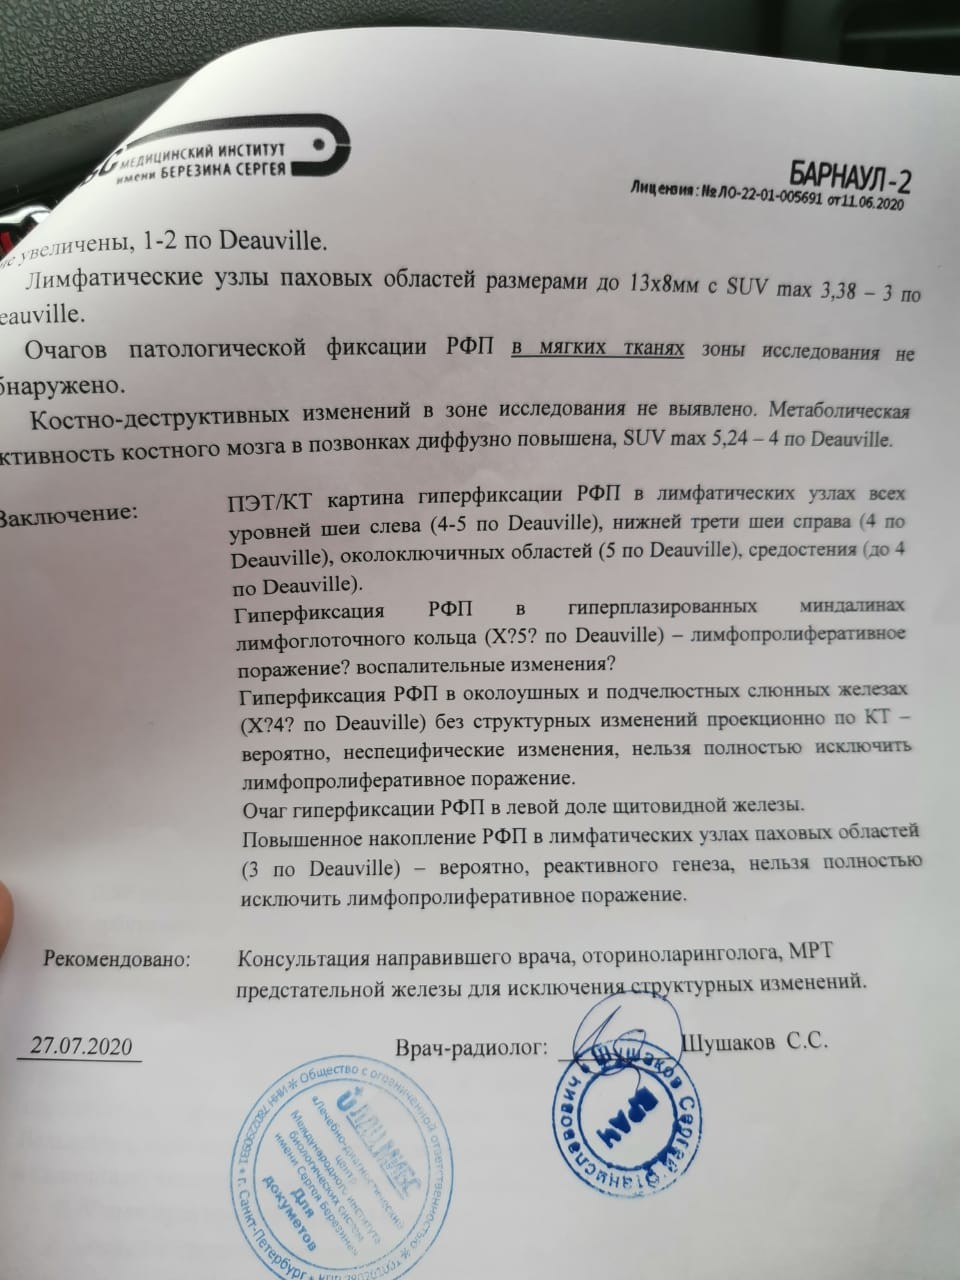

Диагностика лимфомы Ходжкина с помощью ПЭТ и КТ

Раздел: Светлые идеи